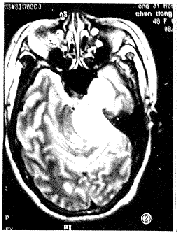

图1 左侧三叉神经鞘瘤。横轴位T1加权像显示肿瘤呈哑铃形,骑跨于中后颅窝之间,呈混杂稍低信号,中颅窝肿瘤边界清楚,可见肿瘤包膜,后颅窝肿瘤发生囊变,边界模糊,无肿瘤包膜。

图2 同图1病例,横轴位T2加权像显示肿瘤呈较均匀高信号,第四脑和脑干受压变形,同侧海绵窦受侵。

6例中5例为单发病灶,1例为多发病灶。其中左侧3例、右侧4例,共7个肿瘤。肿瘤最大为6.4cm×3.1cm×3.0cm,最小为2.8cm×1.5cm×1.0cm。MR检查示5例单发肿瘤呈哑铃状骑跨于中后颅窝之间(图1、2),1例除见骑跨征象外,其另1病灶呈卵圆形位于中颅窝。肿瘤有5个发生囊变,且4个较大的囊腔均位于后颅窝,而2例并发神经纤维瘤病者基本为实性,仅一个肿瘤在中后颅窝均有多个小囊腔(图3、4)。位于中颅窝的肿瘤边界都清楚,周边见完整肿瘤包膜,多呈等或混杂T1长T2信号。而位于后颅窝的肿瘤边界清楚,但大部分无肿瘤包膜,呈长T1长T2信号。注射Gd-DTPA后扫描,肿瘤实体部分均匀强化,囊性部分呈环状、结节状强化(图5、6)。位于中颅窝半月节的肿瘤均累及海绵窦、Meckl氏腔(图7、8),同时还对颞叶深部的海马回等产生压迫。位于神经根的肿瘤对小脑、脑干、桥小脑角池及第四脑室产生压迫,引起相应的MRI表现。